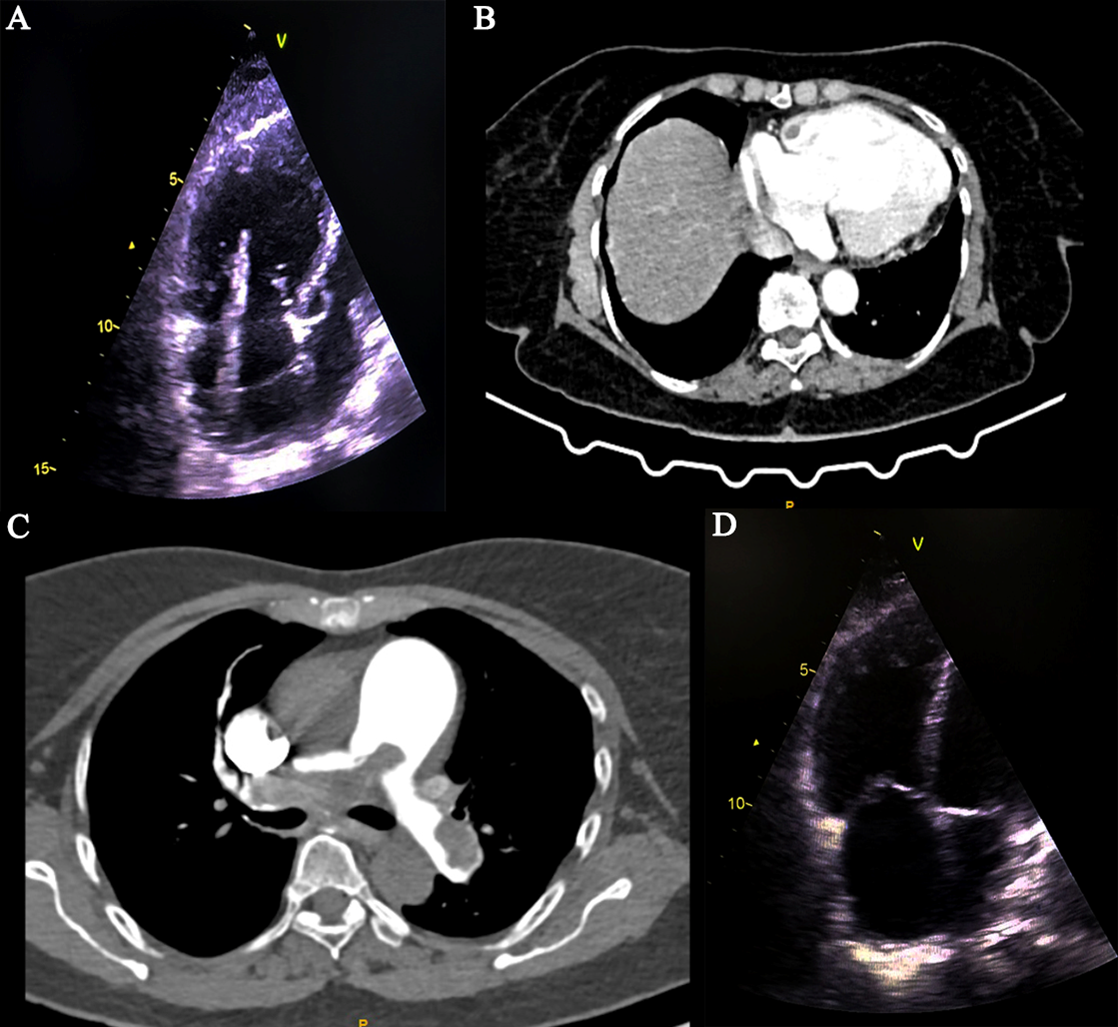

Repeat CT was done to look for resolution of the pulmonary thrombus. However, persistent pulmonary artery thrombus was noted (Figure 2A) and a percutaneous aspiration thrombectomy was planned. The pulmonary artery systolic pressure (PASP) was 71 mm Hg (Figure 2B) and a pulmonary angiogram showed a dense filling defect in the main and right pulmonary arteries (Figure 2C, Video 3). An 80-cm 10-French Flexor sheath (Cook Medical) was taken into the right pulmonary artery over a 0.035-inch Teflon wire. Multiple runs of thrombus aspiration were done with an Indigo system CAT 8 aspiration catheter (Penumbra) in the main, right upper, right lower, and left pulmonary arteries (Figure 2D). A 0.035-inch J-tip separator wire (Terumo) was passed through the thrombus to break it to facilitate suction. The PASP reduced to 57 mm Hg (Figure 2E) and pulmonary angiography showed minimal resolution of the filling defect after thrombo-suction (Figure 2F, Video 4).